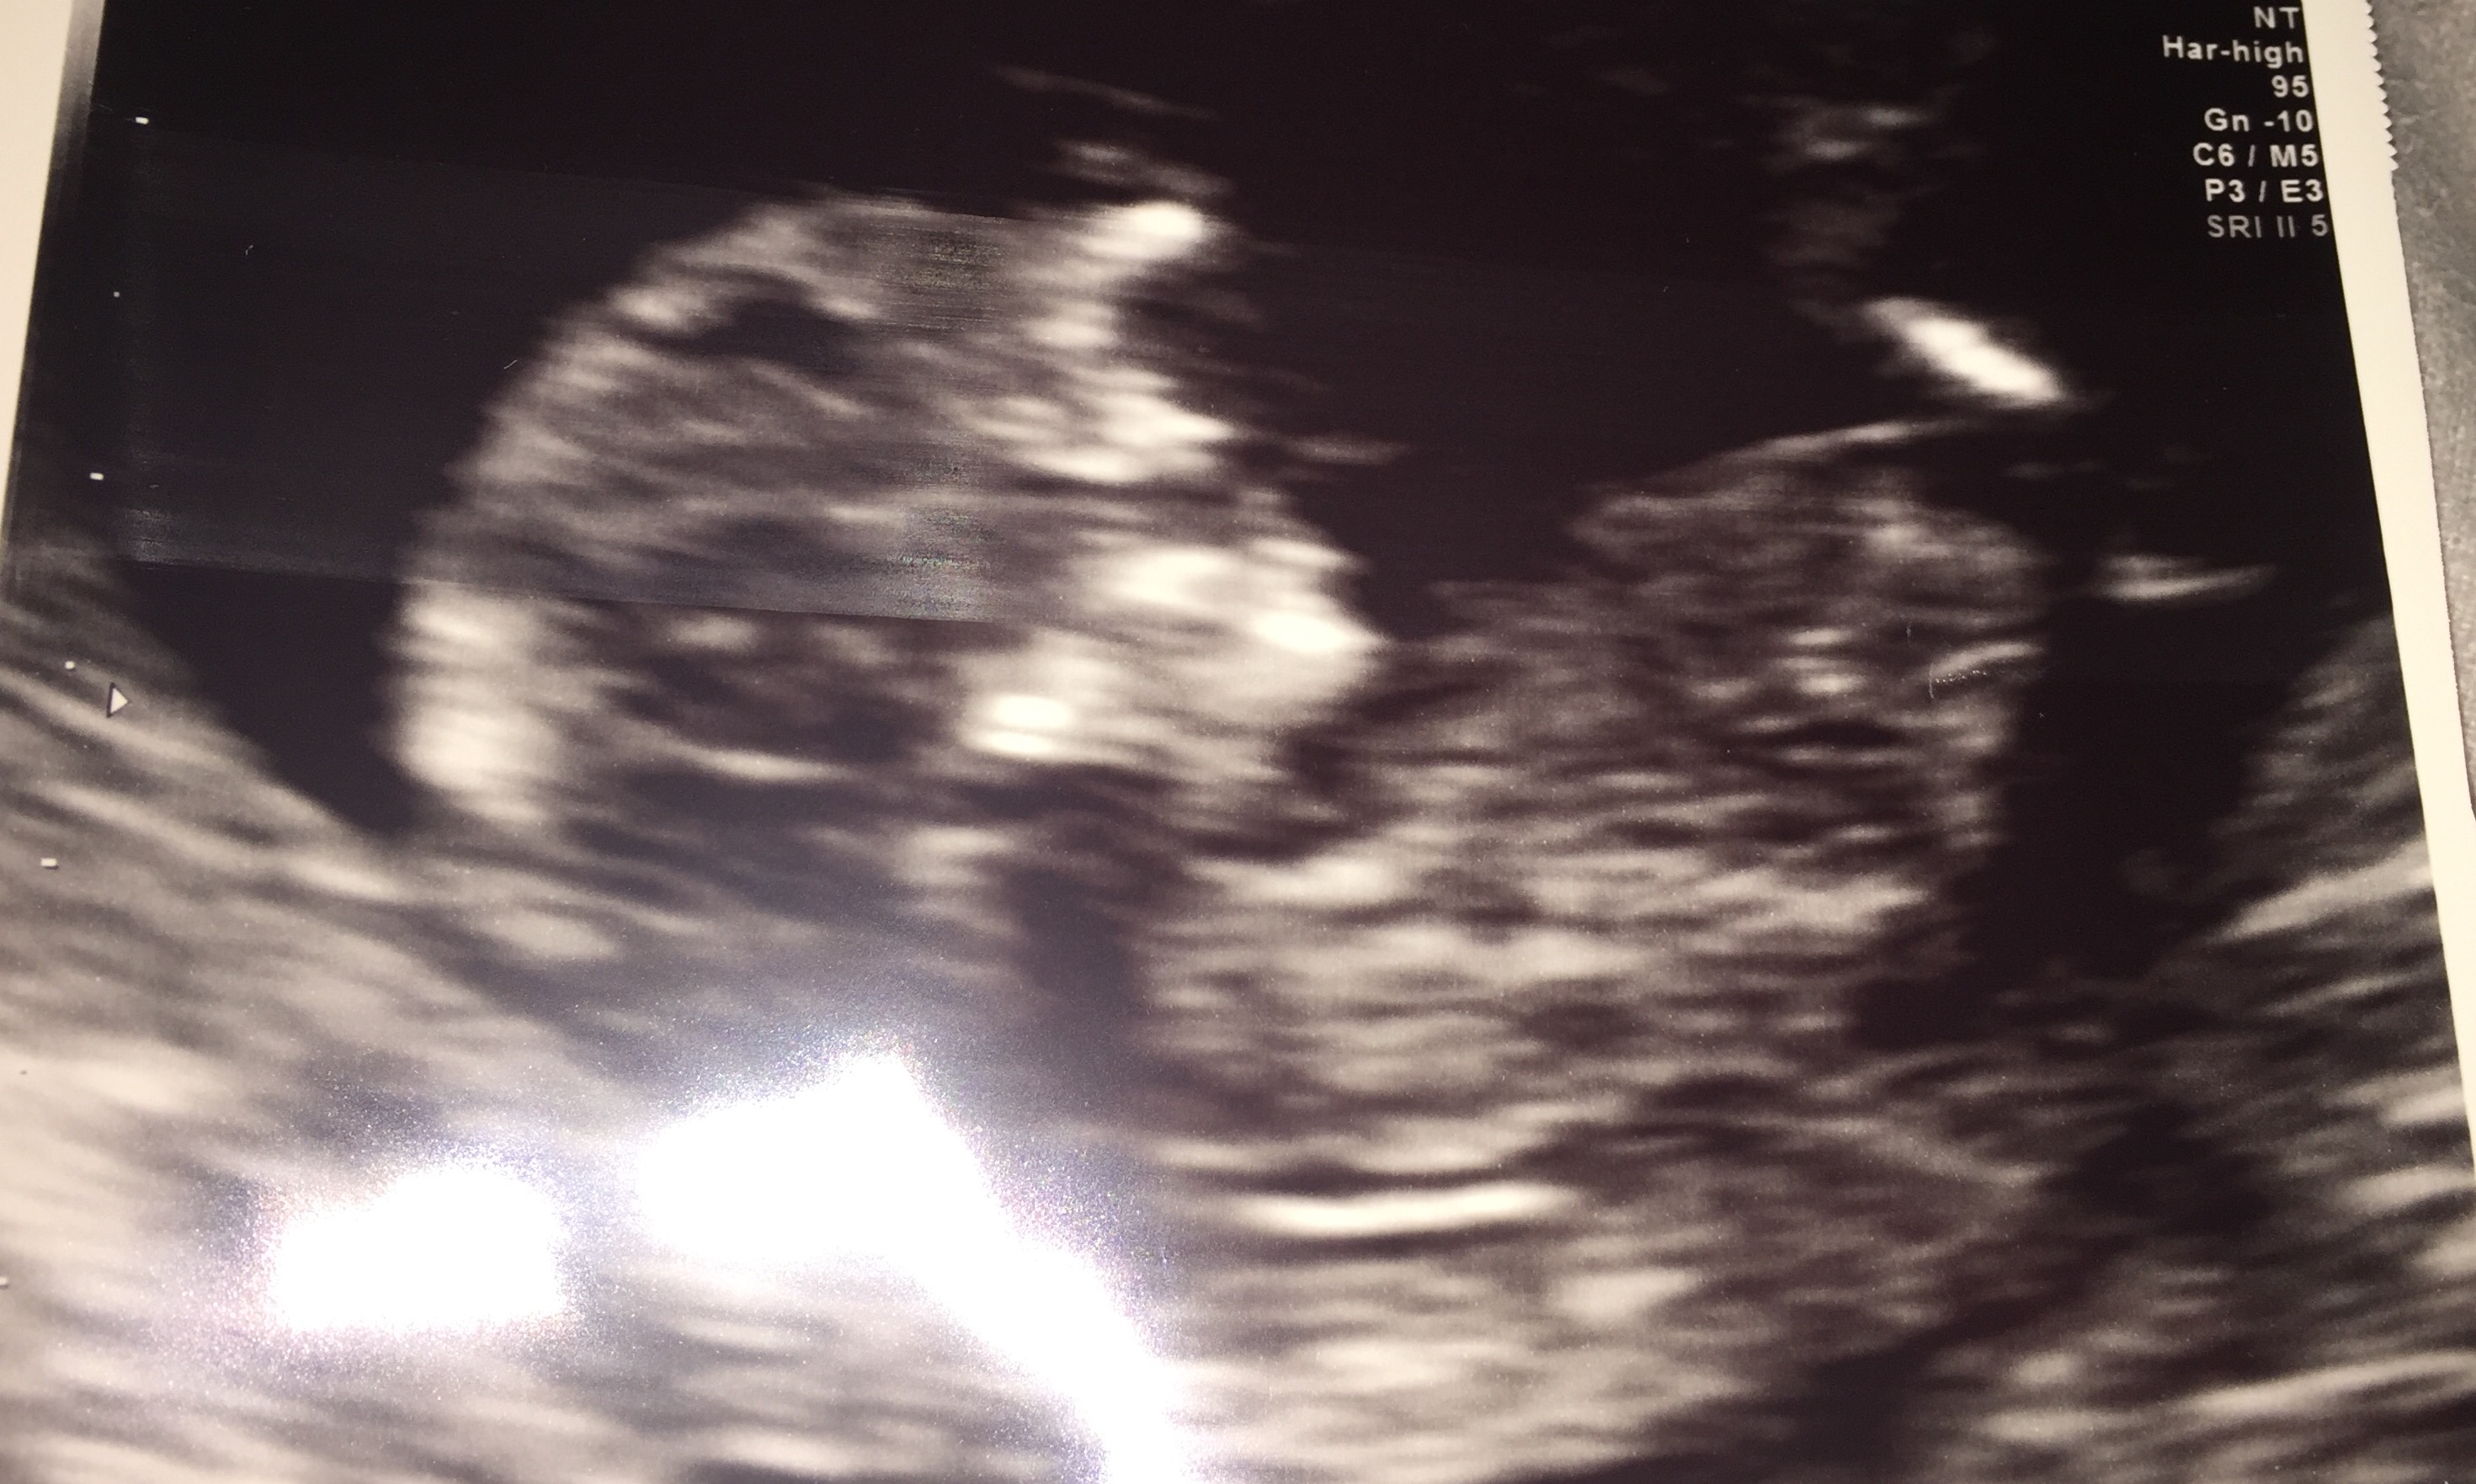

So I went for my first scan, by all my and my doctors calculations I should have been 13+2, however baby is measuring at 12+0 in these pics, so confusing...! Guesses for fun as we don't mind pink or blue this time! May find out but thinking about possibly waiting till birth to find out as I've never done that before! Anyway thank you any any guesses appreciated! X Attachment 33315

This is all I have, thanks for looking xx

Maybe girl, but not entire nub is showing, so it's just a guess.

Just thought I'd update as we have had the 20 week scan, incase anyone has a similar pic and wants to compare. Baby confirmed girl. Strange to be our 2nd girl in a row, I would never have believed this a couple of years ago when I had the two boys one after the other. Didn't sway with either and this baby was a total surprise. Will be fun to even up the household! Xx